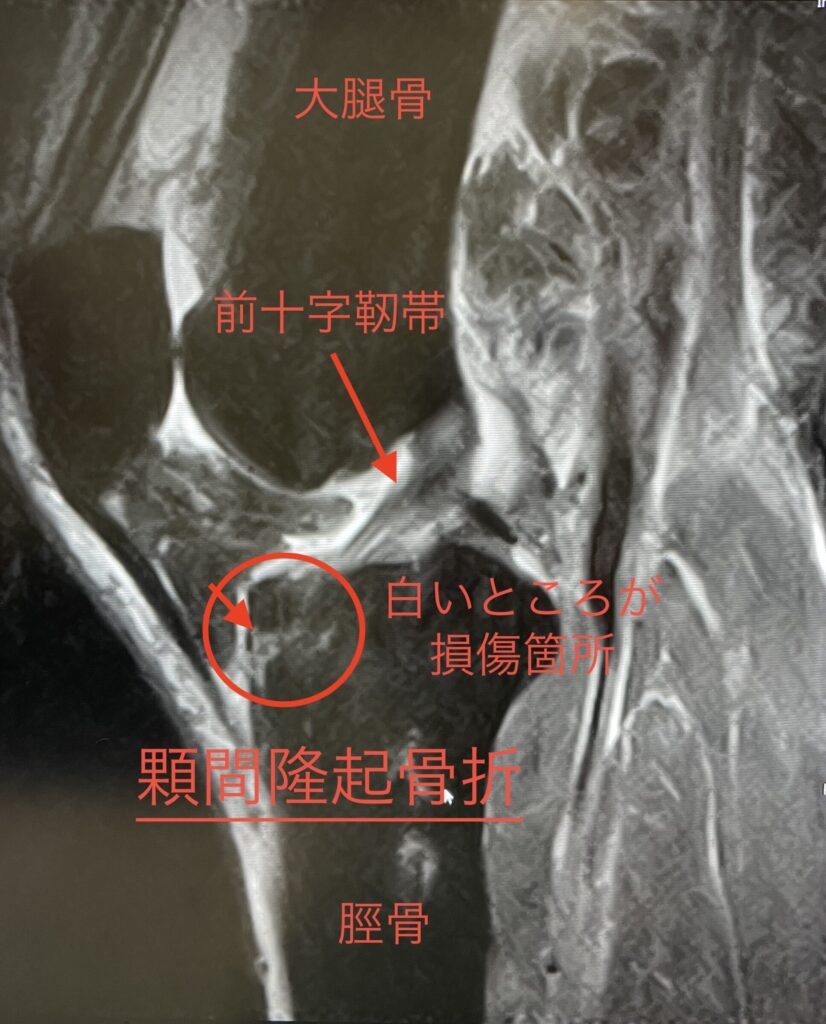

骨折の症状としては主に2つで一つは大腿骨で脛骨(けいこつ)を押し潰しちゃった脛骨プラトー骨折、もう一つは前十字靱帯のつけ根のところが剥離しそうになってる顆間(かかん)隆起骨折。

どちらもレントゲンでは殆ど映らなくてMRIじゃないと分からない状態(写真の丸で囲った所の白い部分が損傷箇所)でした。

症状的に顆間隆起骨折の方が無理すると剥離しちゃうからという事で先生からはとても心配されてます。